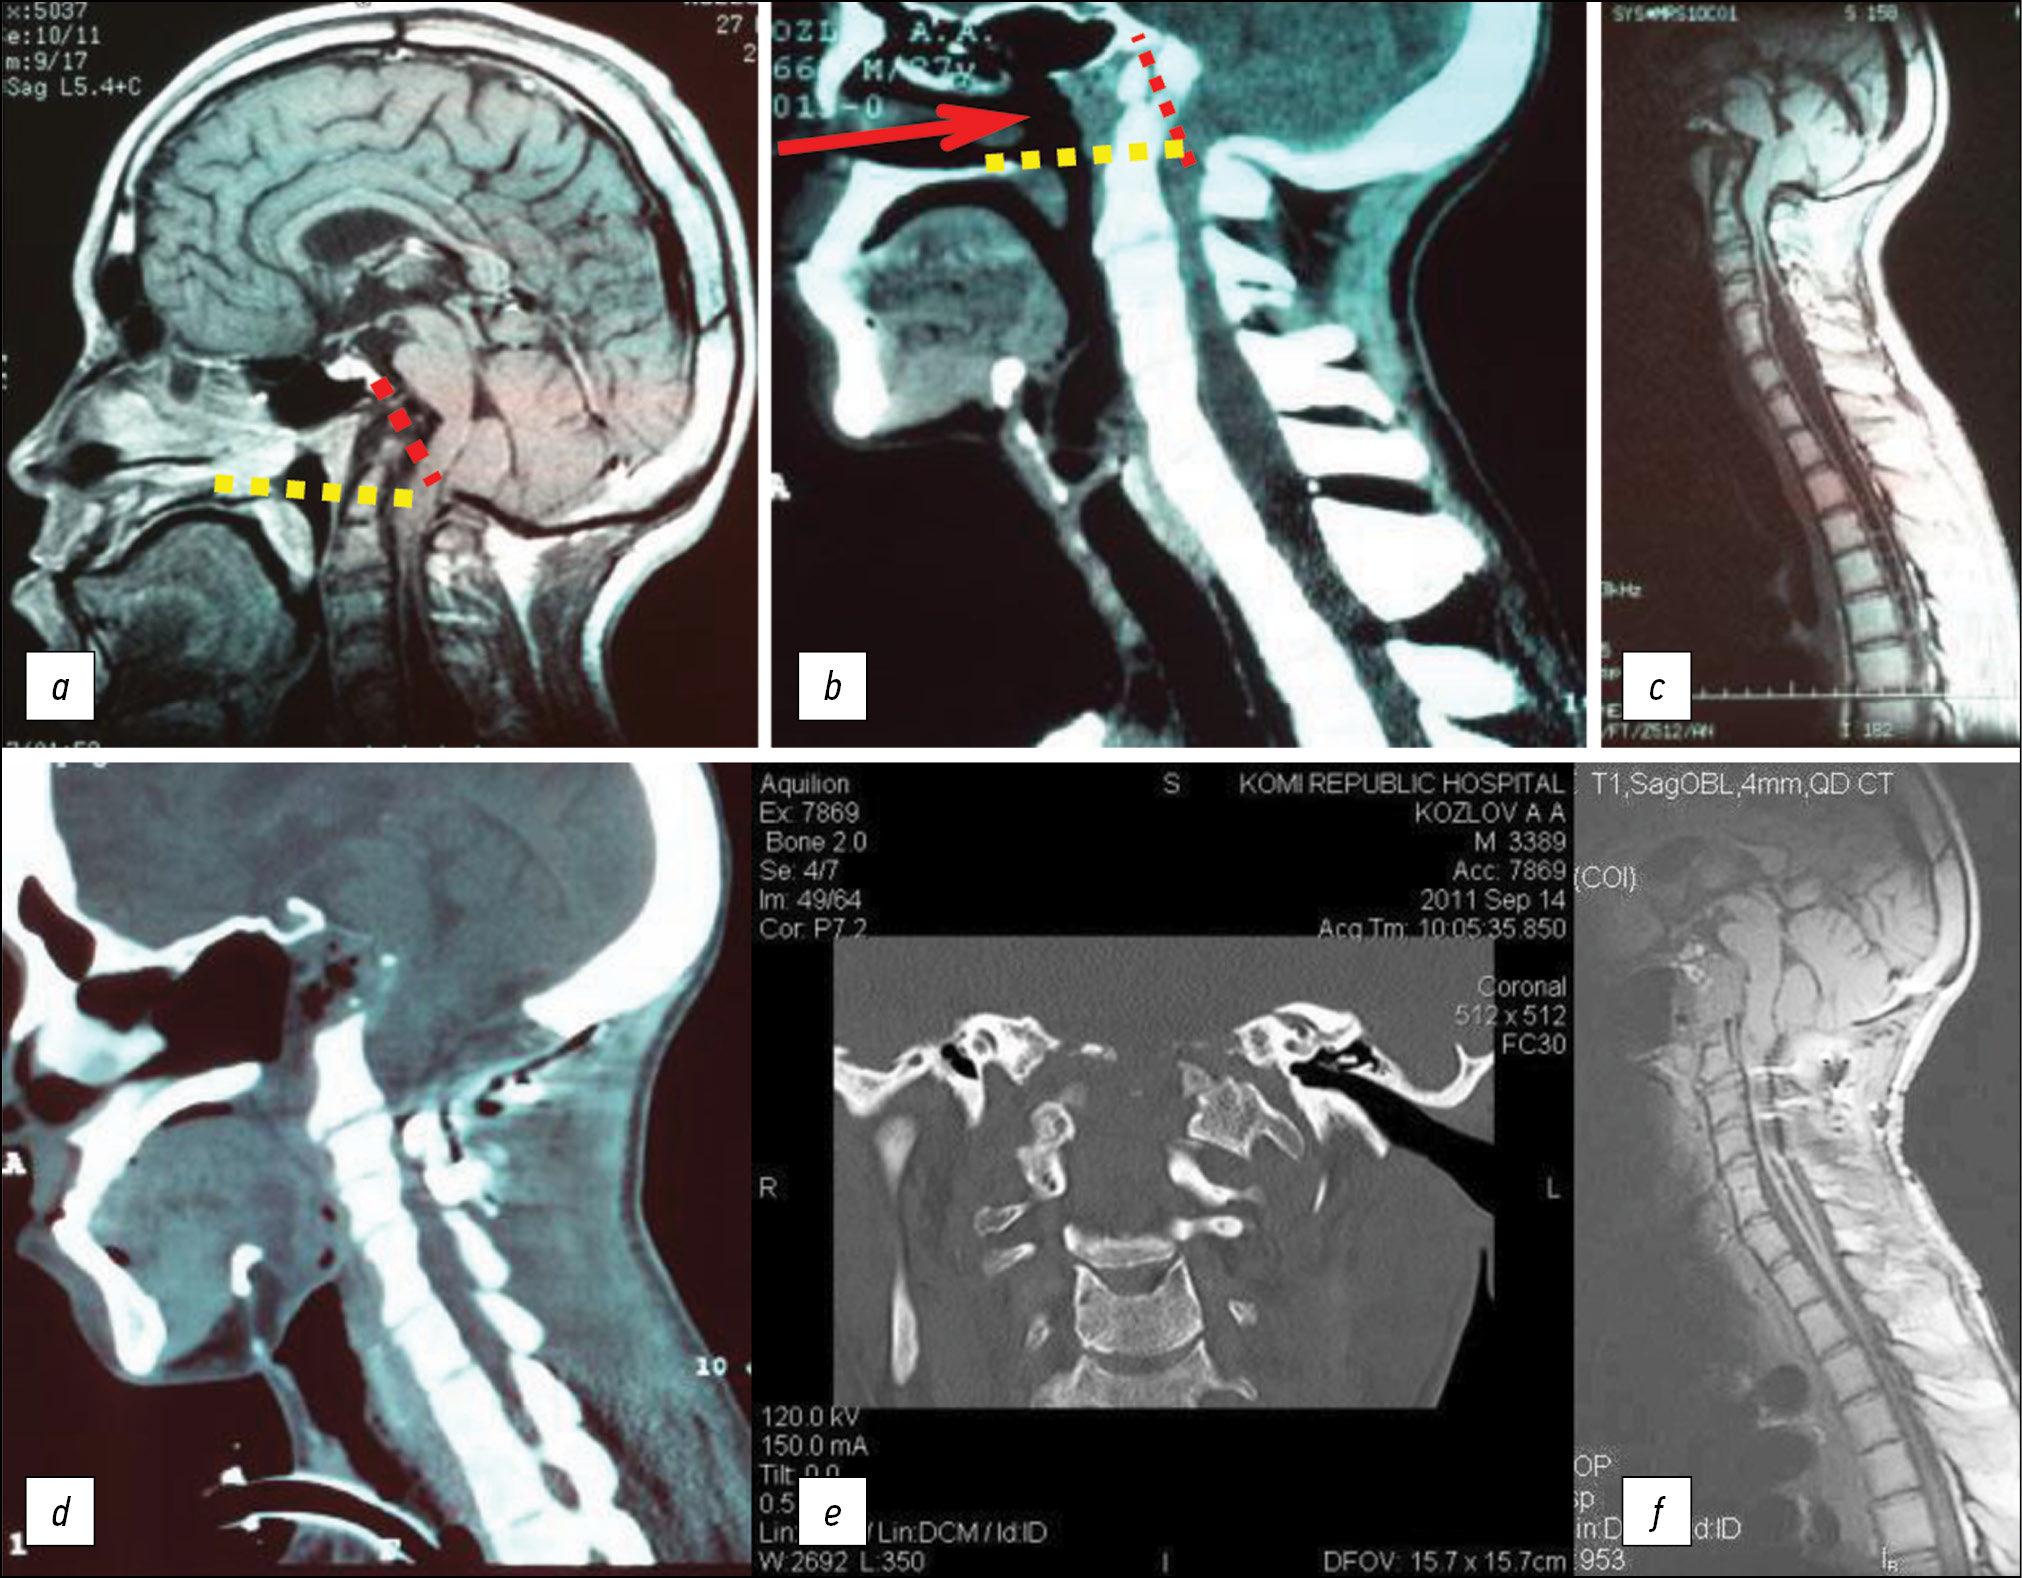

The median duration of hospital stay after odontoidectomy was 18 days ([11.5; 28.5]). The longest hospital stay was 55 days in a female patient with a triple suture dehiscence on the posterior wall of the oropharynx in the postoperative period (clinical example in Fig. 5). Female patient N, aged 13, was admitted to the N.N. Burdenko National Medical Research Center for Neurosurgery. MRI and CT revealed platybasia, an invaginated odontoid process with compression of the stem structures (Fig. 5). In the neurological status, there was spastic tetraparesis (four points), bulbar disorders, and ataxy.

Fig. 5. Neuroimaging studies of patient N., 13 years old, before and after surgery.

Note. а — MRI in T1 mode in the sagittal projection. b — SCT in the sagittal projection. c — SCT in axial projection. Platybasia, invagination of the odontoid is determined. The yellow dotted line is the Chamberlain line. The clinical presentation — a violation of swallowing, speech, weakness in the limbs, unsteadiness and instability when walking. d — SCT immediately after surgery (transoral odontoidectomy) in the axial projection. e — SCT immediately after the operation in the sagittal projection. f — MRI 2 years after surgery in the sagittal projection. There is decompression of the anterior spinal cord. The yellow dotted line is the Chamberlain line. On the 14th day after the operation, the sutures were removed from the posterior pharyngeal wall. The tracheostomy was removed on the 23rd day after the intervention. She was transferred to independent nutrition on the 23rd day after the operation (before that, nutrition was carried out through a nasogastric tube). In the neurological status: regression of tetraparesis, bulbar disorders. On the 43rd day after the intervention, the patient was discharged in a satisfactory condition.